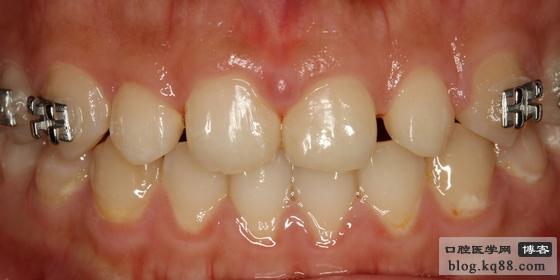

5個(gè)月的正畸治療,平均間隙